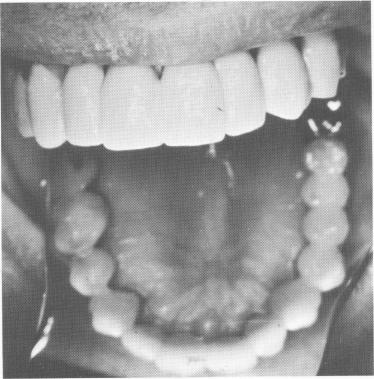

Fig. 15-49. The occlusion and overjet were greatly improved.

3 Occlusion and overjet improved after endosseous blade implantation